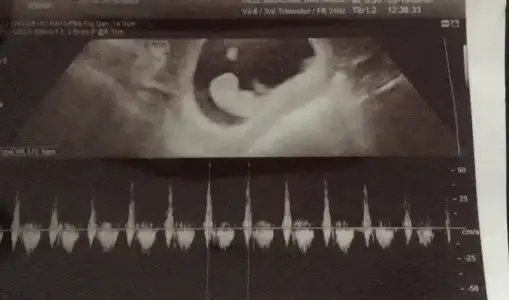

Kaç haftalık baya büyük görünüyor :)Bende bugün doktora gittim kızlar baya kesenin sol tarafında bebek ,hep içime kız doğuyordu şaşırdım![]()